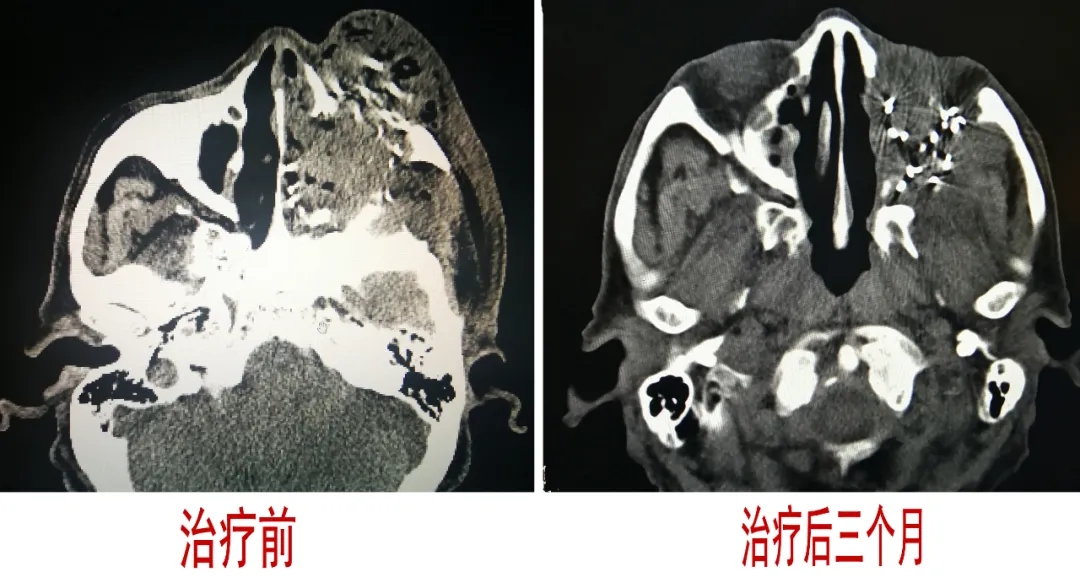

患者,男,81岁,2019年12月,发现左侧颜面部肿大伴疼痛,左侧颜面局部肿的包块进行性增大并疼痛感加重,左侧眼球眼球外突。2020年2月在某医院行头颅CT检查,诊断为上颌窦肿瘤。于2020-07-27入住运城同德医院,入院后与2020年8月3日采用125-碘粒子植入治疗技术治疗。粒子植入术前做TPS计划,术中植入手术顺利、成功、患者无不适感觉,术后进行TPS计划符合率验证。2020年11月8日(术后3个月)来院复诊,患者左侧颜面部肿块消失、外突的眼球回缩至“正常”,患者的左侧颜面部的肿胀、疼痛等不适感觉消失。整体治疗效果明显。

125-碘粒子植入治疗技术先进,对肿瘤局部作用均匀、疗效好、副作用少。125-碘粒子针对肿瘤点对点治疗,定位更准确、局部治疗效果更明显。125-碘粒子具有“无刀手术”效果,对周围正常组织损伤极小,术后2-3天即可出院。